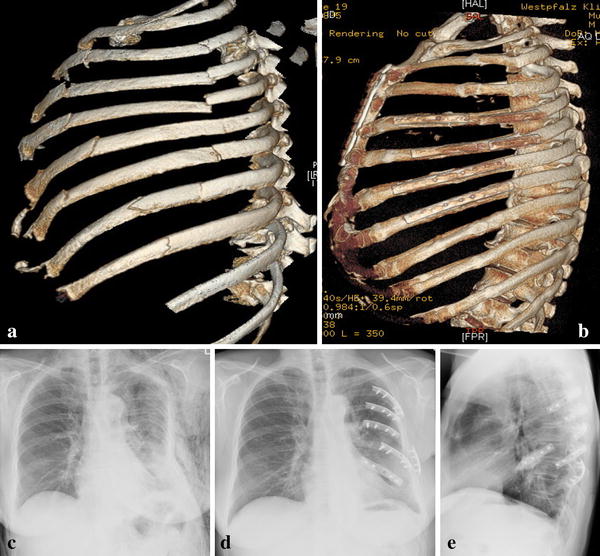

Sternal Injury Rib Injury Clinic

from www.ribinjuryclinic.com